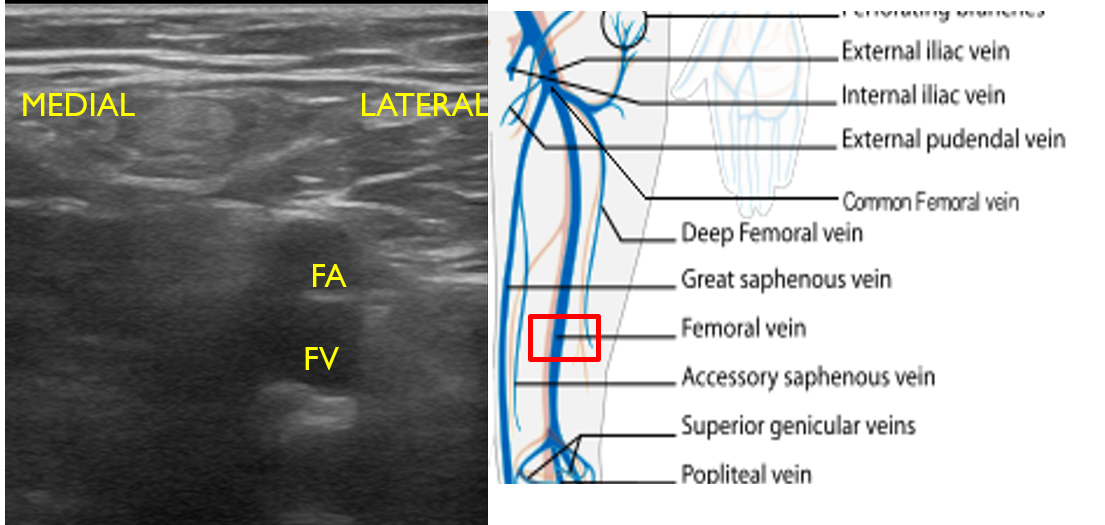

Lower Extremity Deep Venous US Imaging Illustrations International Deep Leg Veins Varicose veins most often affect the veins in the legs. They can be divided into two groups; The veins of the lower limb drain deoxygenated blood and return it to the heart. That's because standing and walking increase the pressure in the veins of the. 10k+ visitors in the past month Deep vein thrombosis (dvt, also called venous thrombosis) occurs. Deep Leg Veins.